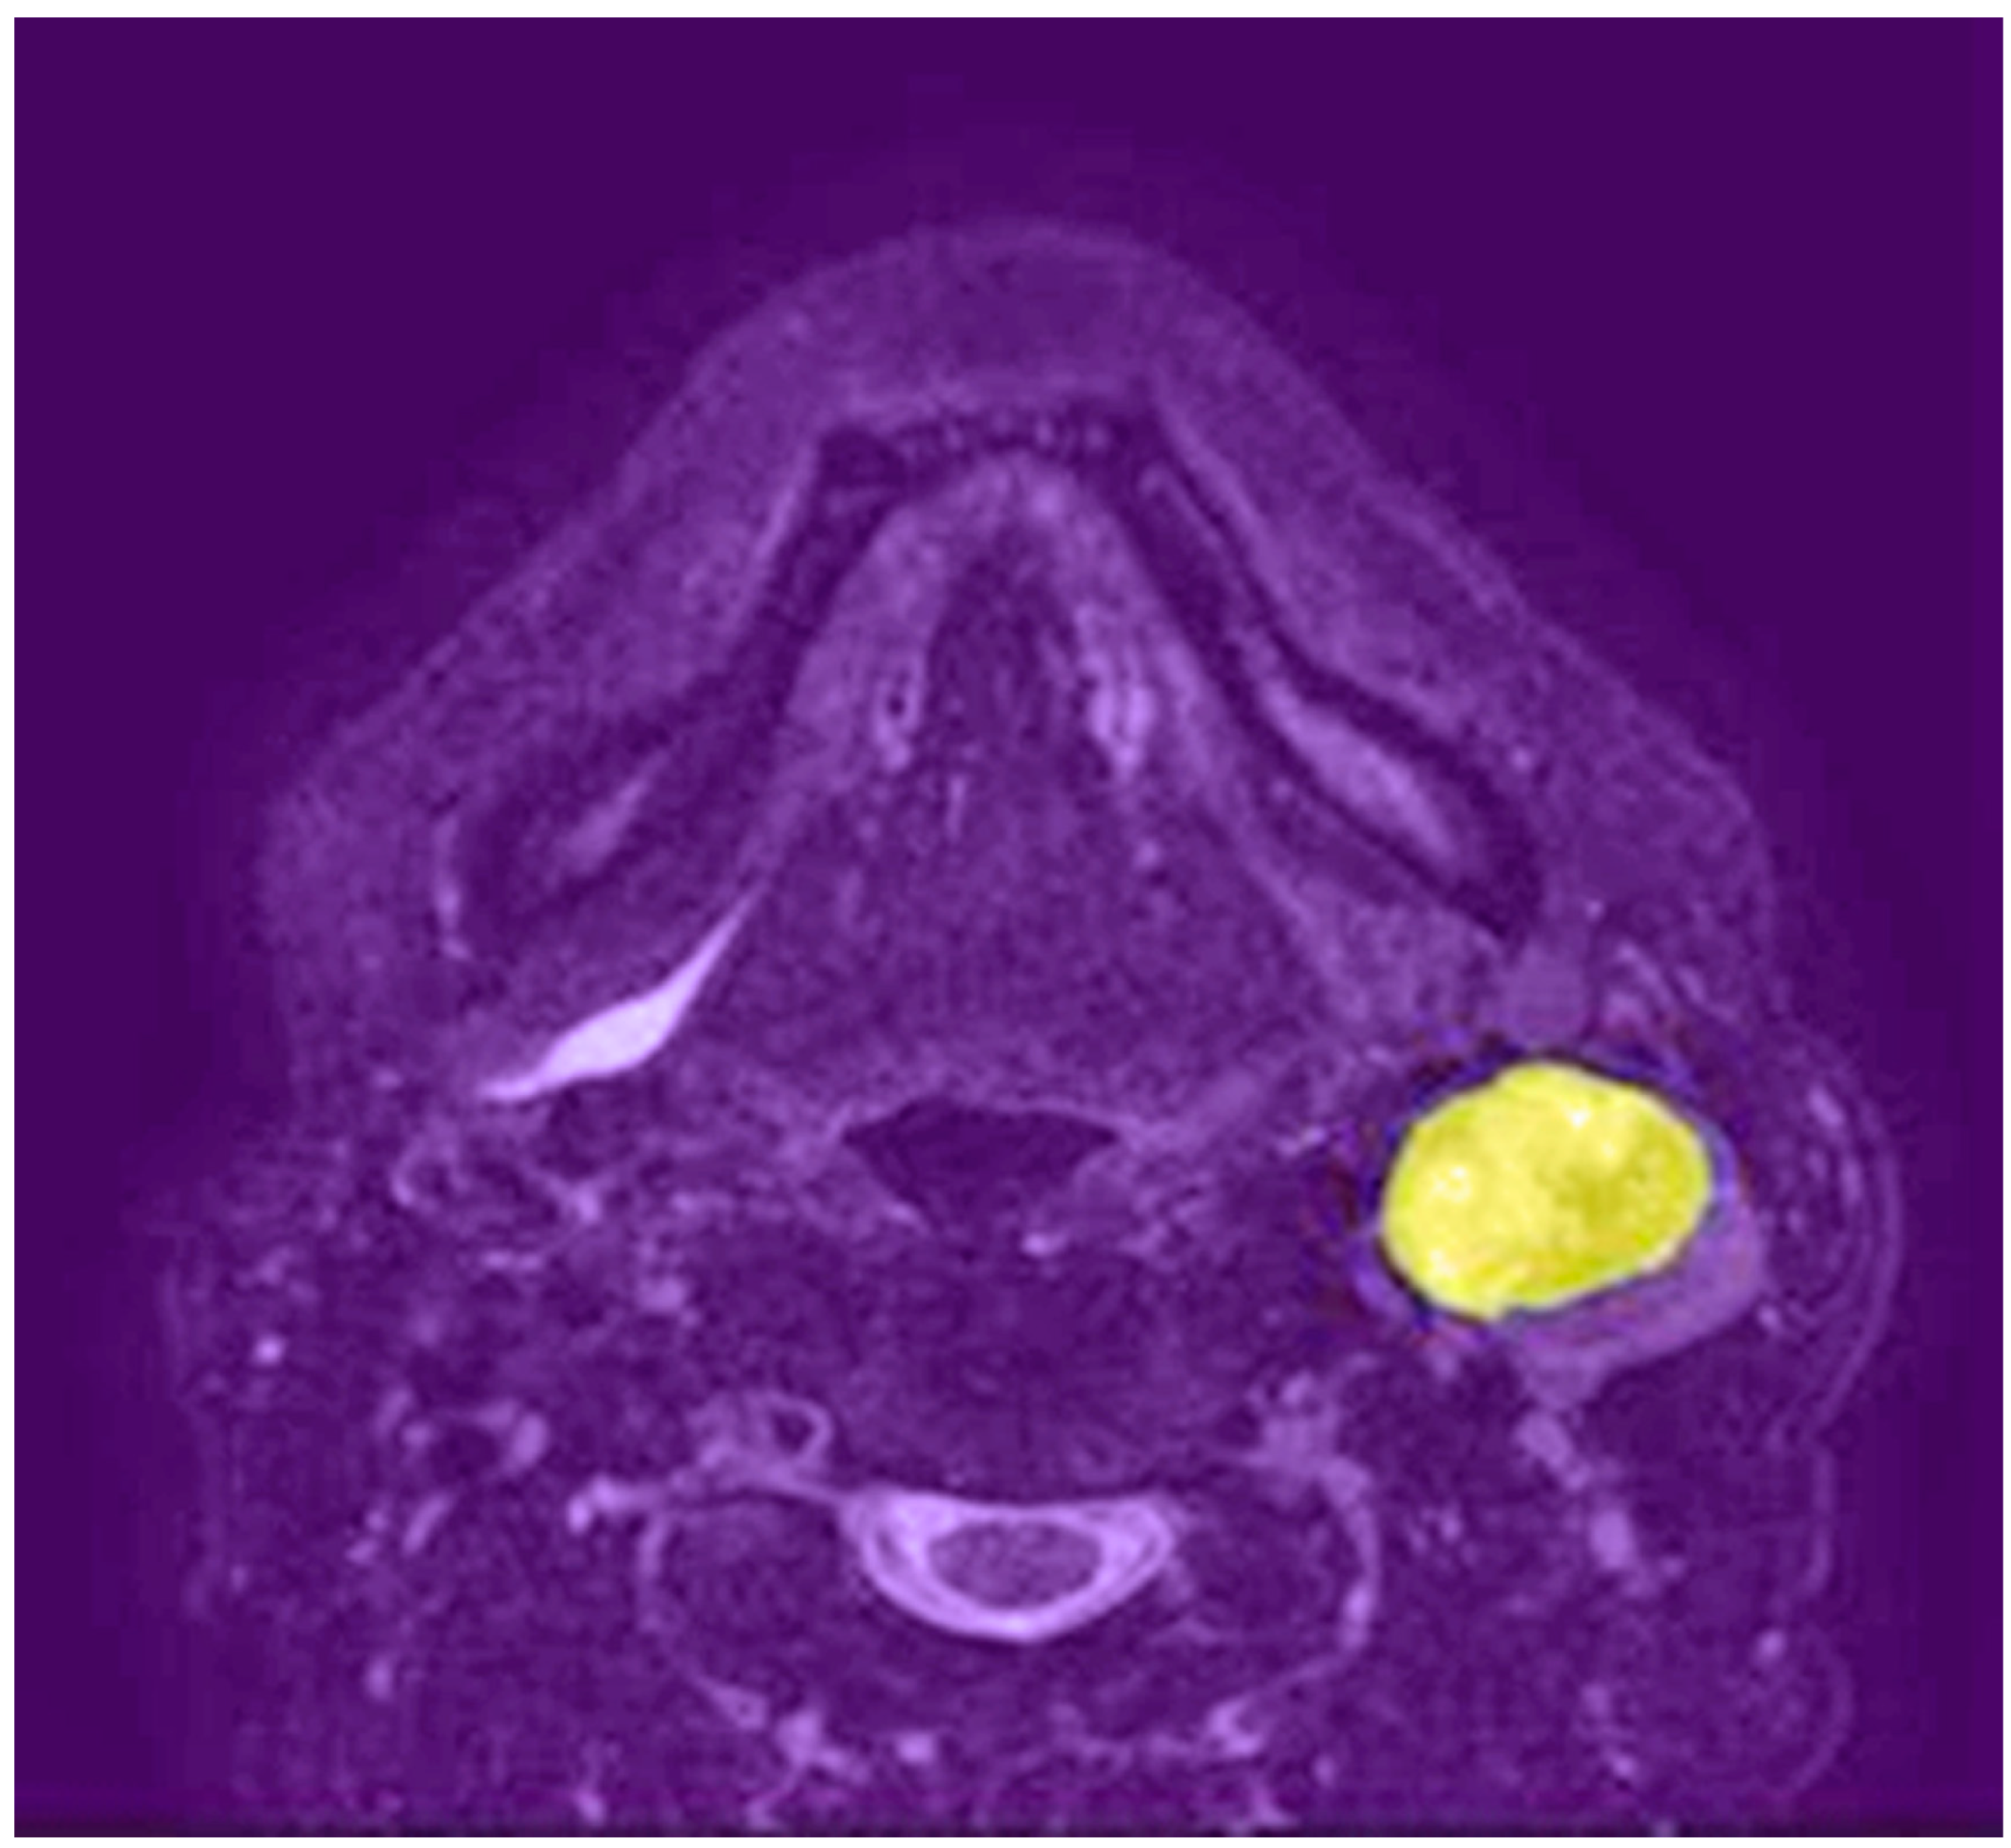

4.1.1. Tumor Detection and Segmentation

4.2.1. Tumor Detection and Segmentation

4.3.1. Tumor Detection and Segmentation